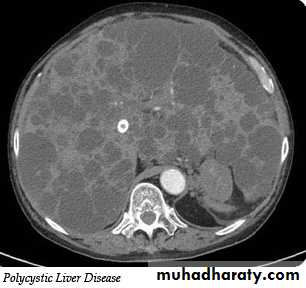

Liver cysts

Simple cysts: may be single or multiple, usually congenital , some are due to infectionMultiple hepatic cysts occur in adult polycystic disease

US features of simple cyst: sharp margin, echofree, with acoustic enhancement

CT features of simple cyst: very well defined margin with water density(HU=0 – 20).

MRI features of simple cyst: low signal on T1 and high signal on T2.

Simple cyst do not show enhancement after IV contrast in CT and MRI